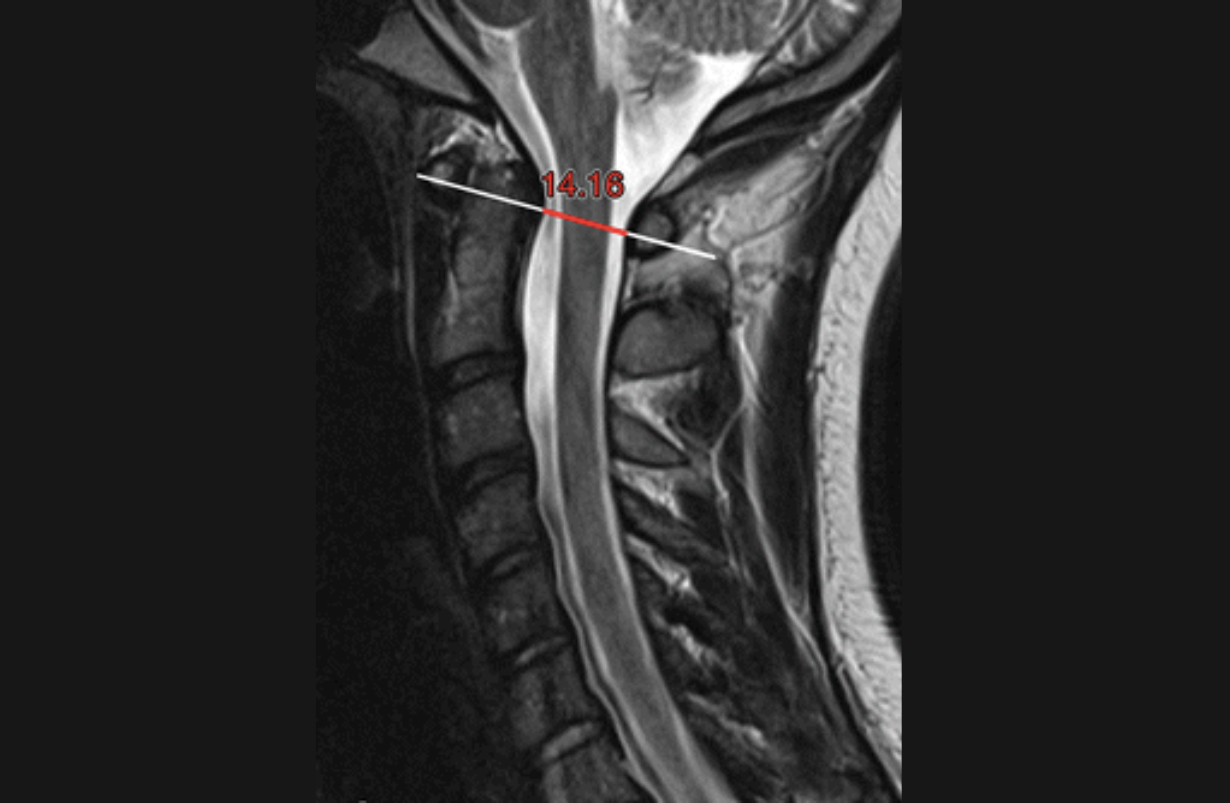

Cervical Spinal Stenosis

Narrowing of the canal the spinal cord passes through within the cervical vertebral column. The usual symptoms are cervical or arm or hand pain or numbness or paraesthesias that worsen with extension.Sometimes lower extremity reflexes are elevated.